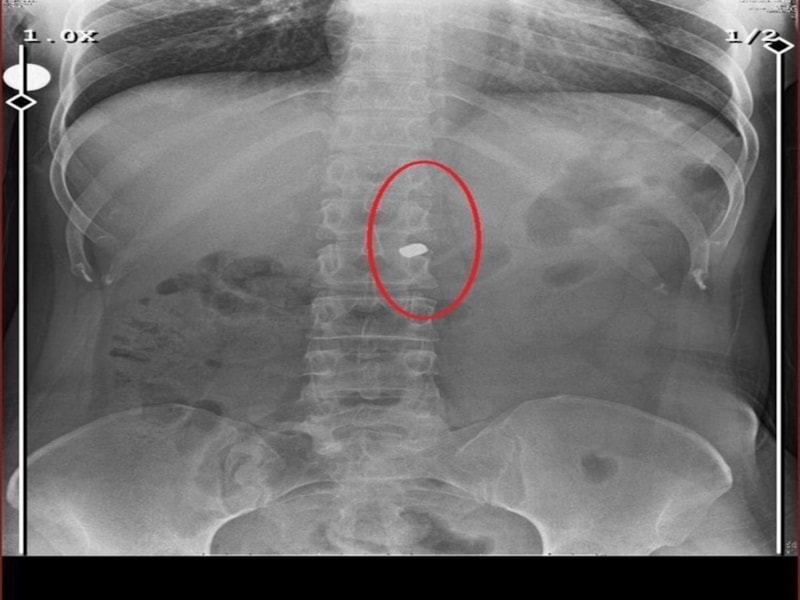

Özaslan, beline ve göğsüne isabet eden kurşunlarla olay yerinde hayatını kaybetti.

İlyas Sarıkaya, sevgilisi Fatma O.'yu da 8 kurşunla vurup, yaraladı. Arkadaşı Özaslan'ın cesedini önce çarşafa sonra da streç filme sarıp bantlayan Sarıkaya, eczaneden aldığı sargı bezi ve ilaçlarla pansumanını yaptığı sevgilisine yaralı haldeyken 21 gün boyunca cinsel saldırıda bulundu.